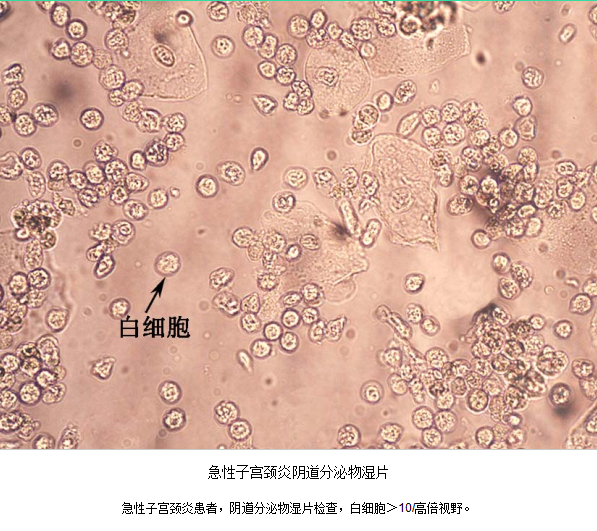

(2)阴道分泌物湿片检查白细胞>10/高倍视野。

急性子宫颈炎患者,子宫颈管脓性分泌物涂片作革兰氏染色,中性粒细胞>30/高倍视野,